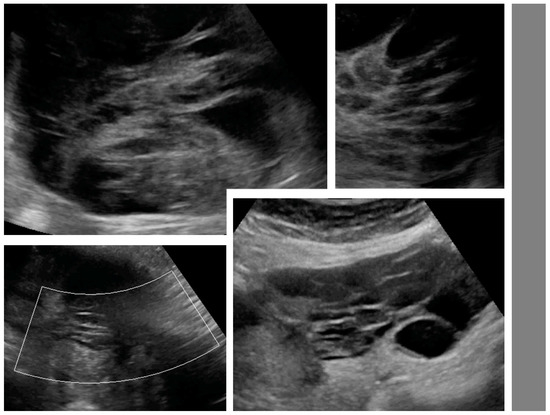

Figure 2.

Necrosis sign [7] in tumor solid portions. Arrows indicate area suspected for necrosis. White dotted line is a measurement of the tumor.

Figure 3.

Layered structure of multilocular tumors.

Figure 4.

Solid papillary projections (arrows) growing from the septa and inner wall. White dotted lines are measurements of the tumor.

After the collection of cases for the study was closed, a new observation was noted (by M.S.) when analyzing the videoclips of ovarian mCRC in detail. A tree-like sign was detected in multilocular-solid tumors, with parallel, closely-localized, septa (“trunk”) later branching in different directions (“branches”), forming an image resembling a tree (Figure 5, Video S3). Interestingly, the tree-like sign was not detected in any of matched controls with primary OC.

Figure 5.

Tree-like sign in a multilocular-solid tumor. White arrows indicate the “tree trunk”; yellow arrows indicate “tree branches”.